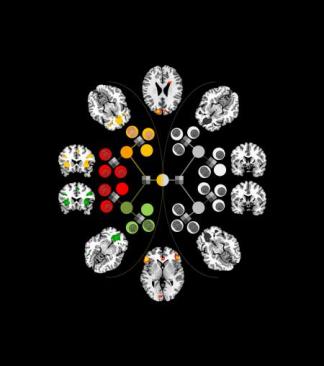

Caltech researchers used a combination of computational modeling and behavioral and fMRI data to pick apart the roles of various brain regions involved in a type of behavioral control. The circles (some bearing coins) and shaded squares relate to a decision-making task given to subjects in the study. Credit: Caltech/Sang Wan Lee/Neuron/Elsevier

Researchers compared the fMRI data and choices made by the subjects against several computational models they constructed to account for behavior, and the model that most accurately matched the experimental data involved the two brain systems making separate predictions about which action to take in a given situation. Receiving signals from those systems, the arbitrator kept track of the reliability of the predictions by measuring the difference between the predicted and actual outcomes for each system. It then used those reliability estimates to determine how much control each system should exert over the individual’s behavior. In this model, the arbitrator ensures that the system making the most reliable predictions at any moment exerts the greatest degree of control over behavior.